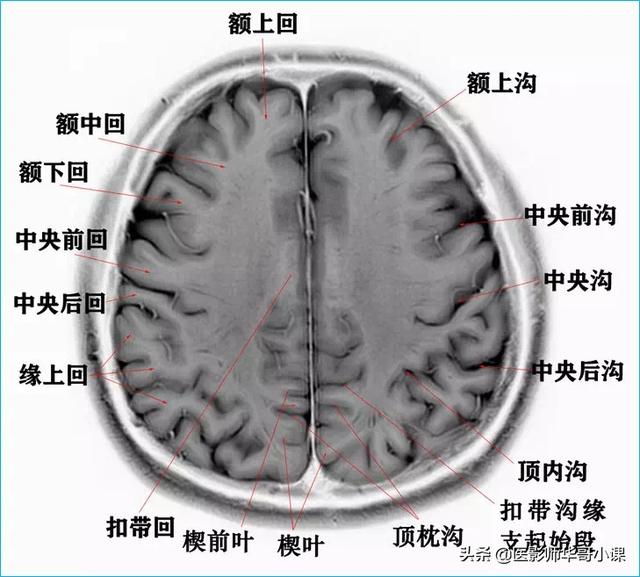

颅脑主要包括大脑、小脑、脑干、间脑,其中大脑又称为端脑,是人体的司令部,管辖人体的躯体活动、精神活动以及感觉行为等;脑干和小脑位于后颅窝的位置,脑干自上而下分为中脑、脑桥、延髓,脑干又称为生命中枢,对人体非常重要,因为脑干具有管辖呼吸和循环的初级生命中枢。其中大脑分为5个脑叶,分别是额叶、顶叶、颞叶、枕叶以及内侧面的岛叶。间脑分为上丘脑、下丘脑、后丘脑、背侧丘脑和底丘脑,背侧丘脑是一个重要的结构,是感觉传导路的重要中继站。颅脑包括颅骨和颅骨内的脑组织。颅骨由顶骨,颞骨,枕骨,额骨,以及颅底骨构成。颅骨构成的颅腔主要作用是保护脑组织。颅内的脑组织主要包括大脑,小脑,脑干。表面覆盖有软脑膜和硬脑膜,大脑分为左右两侧大脑半球,根据解剖位置又分为颞叶,枕叶,顶叶,额叶,各脑叶功能不尽相同。小脑也分左右半球。脑干分为延髓,脑桥和中脑三部分。